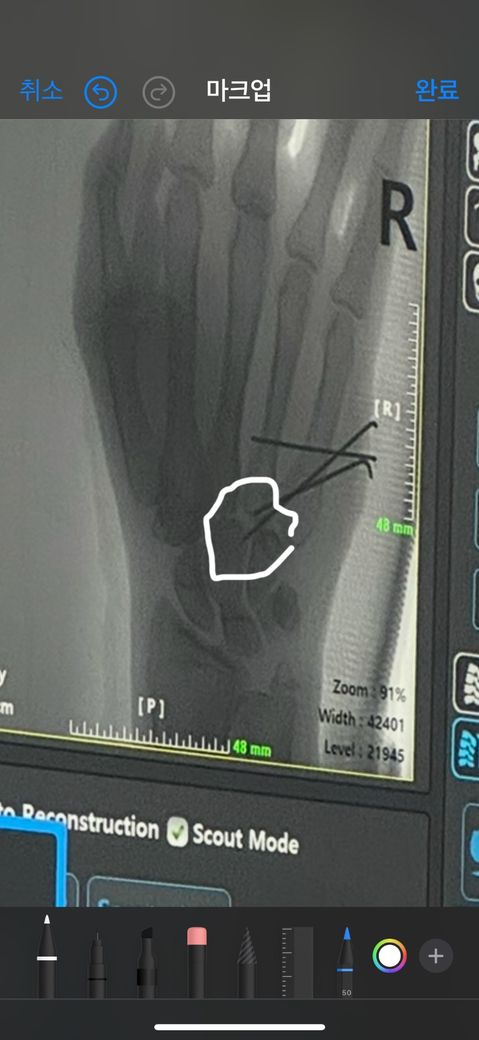

골절로인해 핀고정술을 받은지 3주정도 됬는데 손목통증이 너무 지속되고 심해서병원에 여러번 말해도 약을 더주겠다는 말밖에 없습니디 손목에 움직임이 있을때 저부위가 너무 아프고 손이 엄청 떨리는데 저 핀이 저기까지 박히는게 맞는걸까요??

골절의 상태에 따라 핀을 어디까지 박히는지는 주치의에 판단하에 정해지기엔 지금으로썬 핀의 위치를 확인하긴 어렵습니다.

투시영상이기 때문에 어느 부분에 골절이 생긴 것인지 알기가 어려워 pinning 이 적절한지 여부를 말씀드리기는 어려운 것 같습니다. 단지 현재 불편함으로 인하여 여러번 진료를 받았으나 특별한 조치가 없었던 것으로 보아서 치료에는 크게 이상이 있는 것은 아니지 않을까...하고 어렴풋이 예상은 됩니다.

• 단편적인 정보만 놓고 구체적으로 어떻다 이야기를 하기는 어렵습니다. 구체적으로 어느 부위의 골절에 어떠한 수술을 받았는지 등 자세한 정보가 필요하며, 엑스레이 사진 또한 한 각도에서 촬영한 한 장을 놓고 철심이 적절하게 박힌 것인지 어떤지 파악을 하고 판단을 내릴 근거가 충분치 않습니다. 유감스럽지만 올리신 글의 내용을 토대로 적절성을 평가 받으시기는 어려울 것으로 사료됩니다.